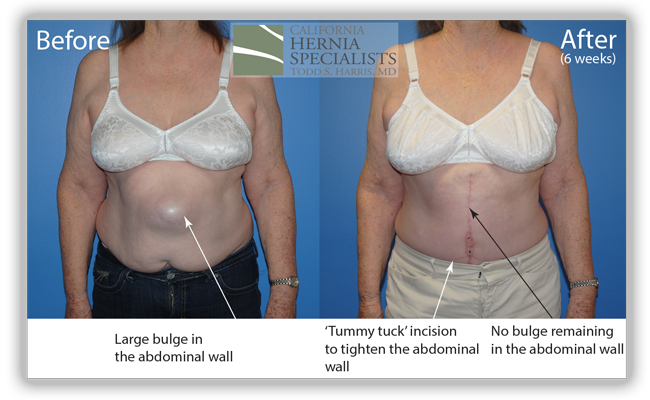

A 73 year old female had gallbladder surgery over 20 years ago. After that surgery she developed a small hernia at one of her incisions. This incisional hernia was repaired and she did well for over 10 years. Then the hernia returned and she underwent a second hernia repair. This only lasted for several years and the hernia returned. She had a 3rd attempt at hernia repair which only lasted several months before she noticed the bulge return.

She presented to California Hernia Specialists for evaluation and possible treatment. On examination it was clear that she had severe weakness of the muscles surrounding the hernia which was likely contributing to the repeated recurrences after her surgeries. Simply patching the hole in her muscle would not bring the healthy muscle back together and give her the best chance at preventing the hernia from returning. Thus laparoscopic hernia repair was not our recommendation.

Instead we discussed open hernia repair with a large incision to repair the damaged muscle and to remove excess skin and fat once the muscle was repaired. Below are a number of pictures including before and after photos, as well as photos taken during her surgery.